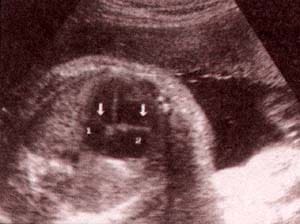

| fig 31. válvulas a-v. válvula mitral (1). válvula tricúspide (2). | fig. 32. válvulas a-v.válvula mitral (1). válvula tricúspide (2). |